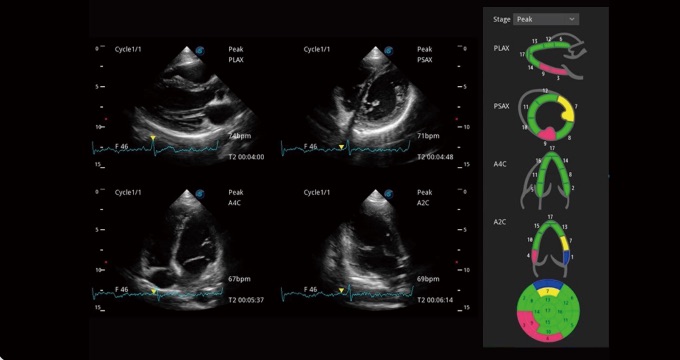

支持運(yùn)動(dòng)和藥物負(fù)荷協(xié)議、多心動(dòng)周期存儲(chǔ)選擇,為臨床觀察心肌負(fù)荷狀態(tài)下的室壁節(jié)段運(yùn)動(dòng)、評估心肌缺血狀態(tài)提供更多的解決方案。